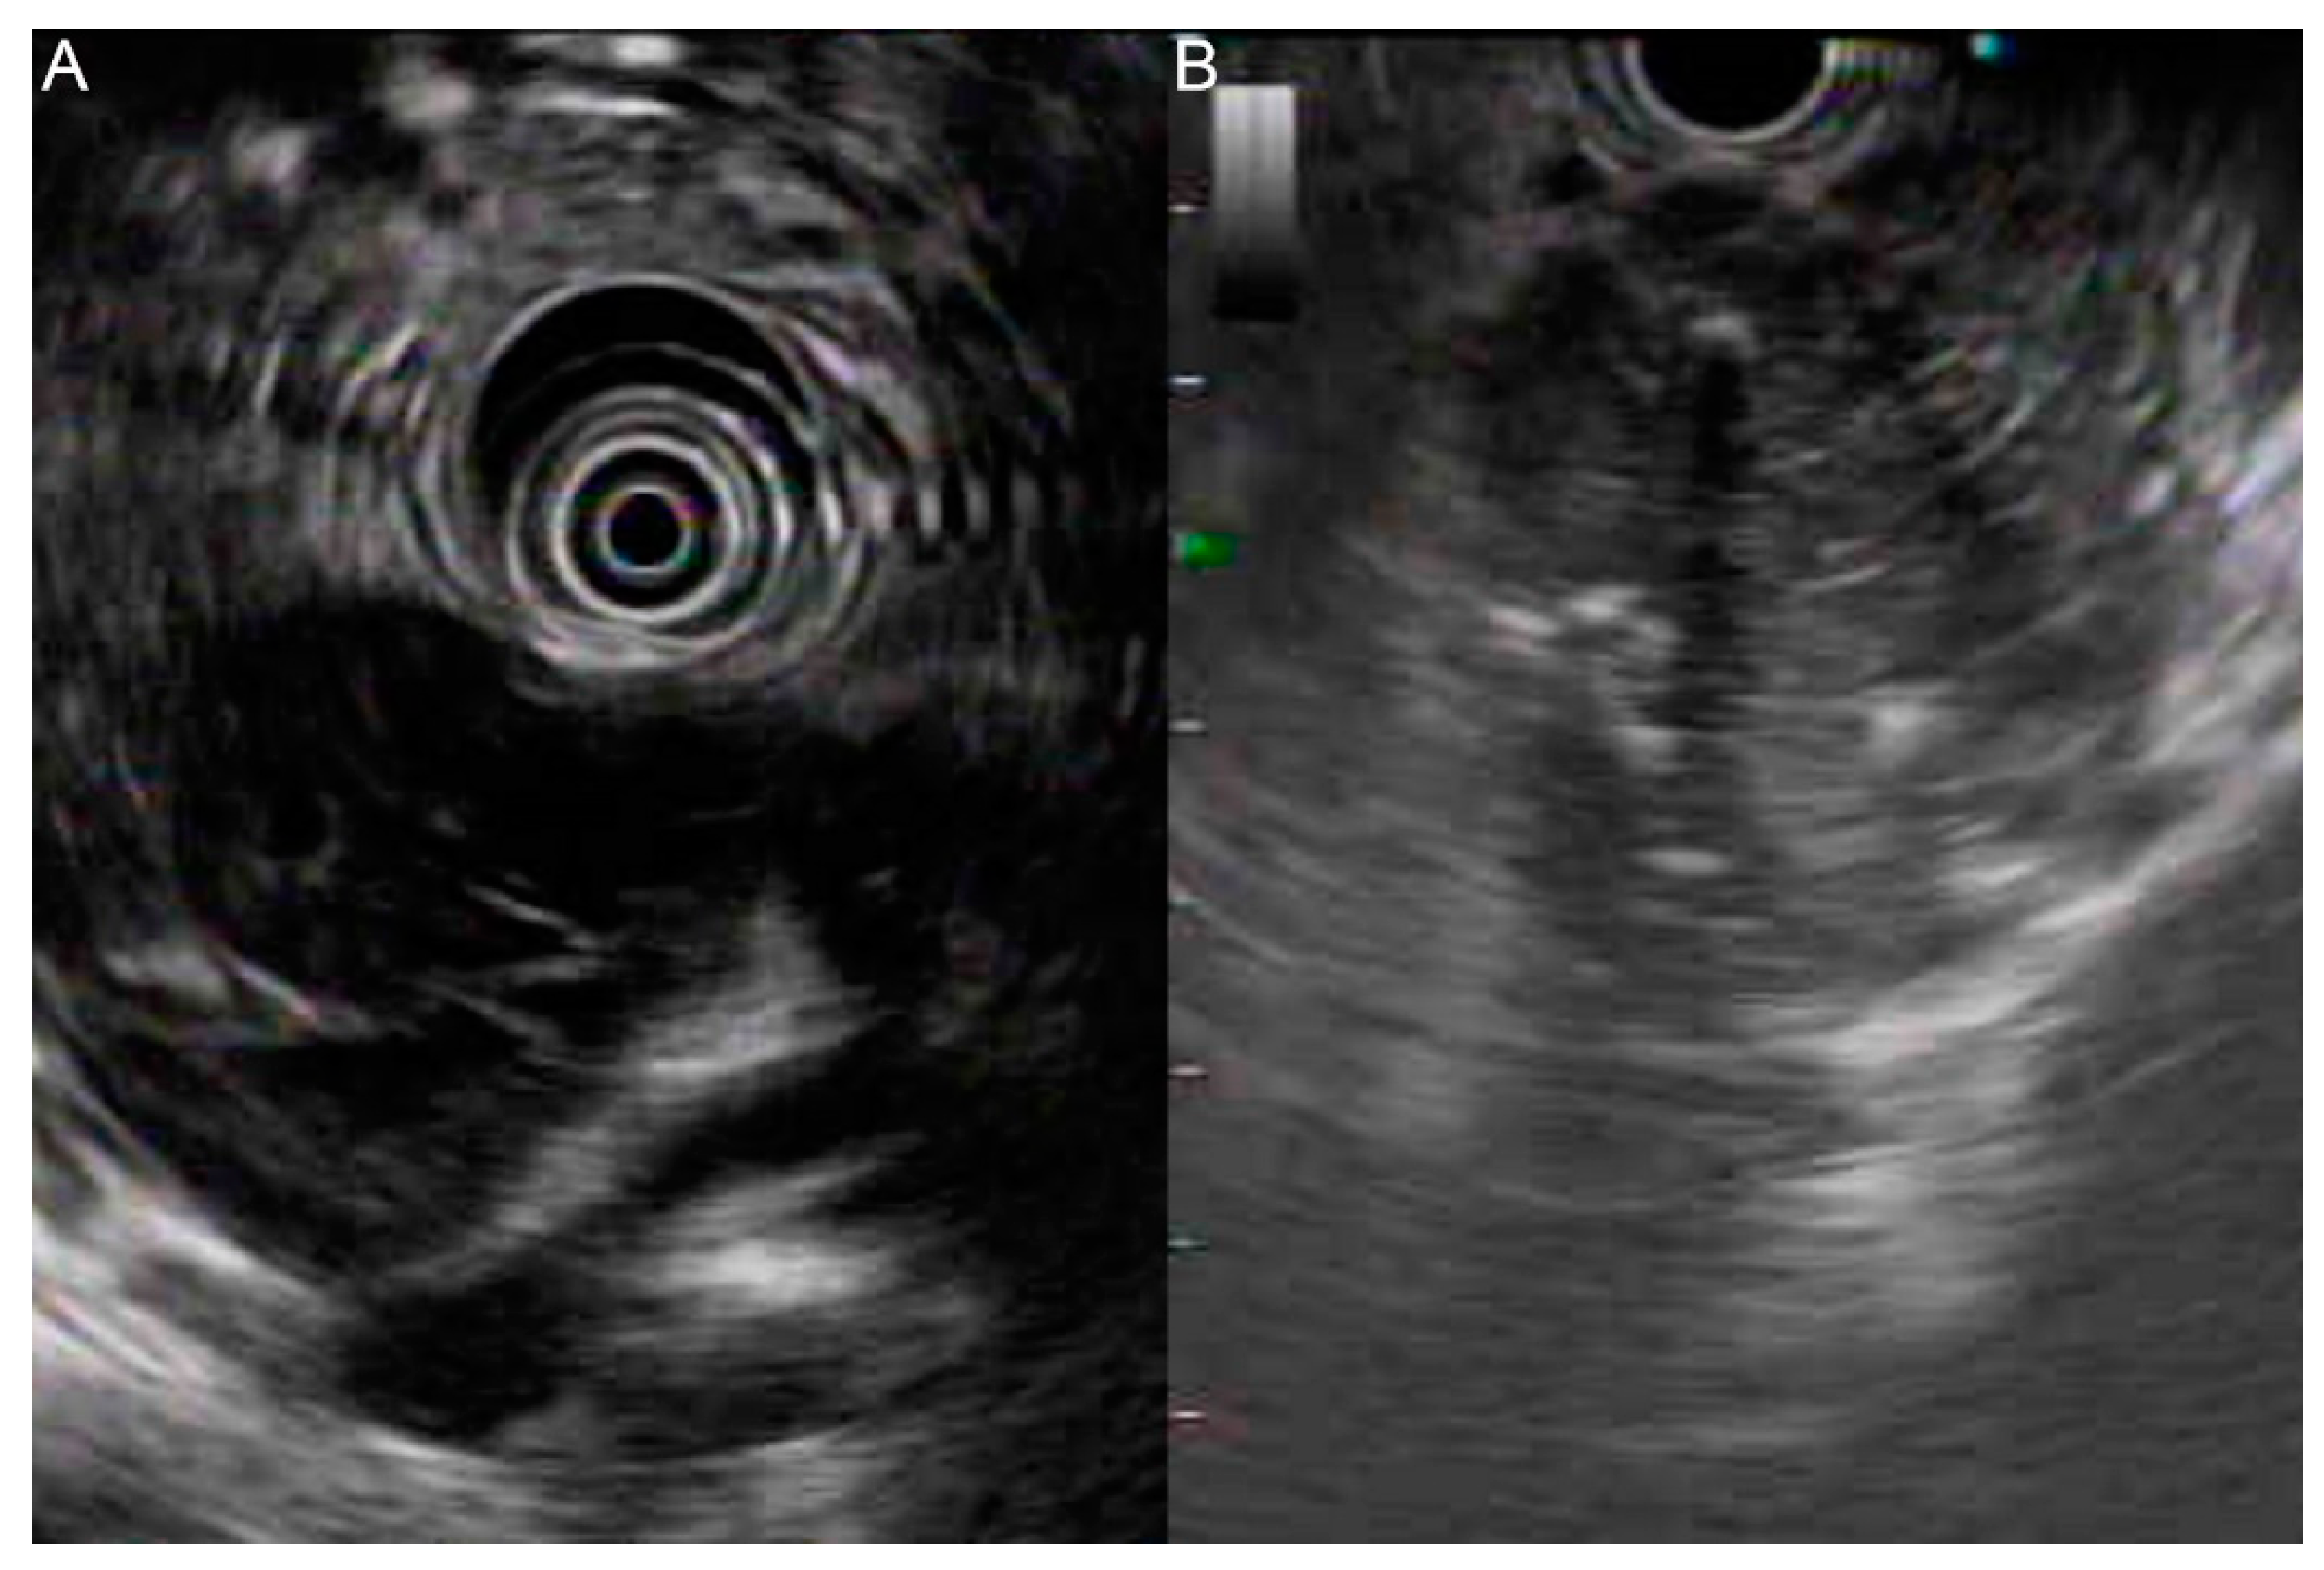

Endoscopic ultrasound (EUS) revealed a heterogeneous hypoechoic lesion with a cystic component around the pancreatic head, measuring 50.1 mm× 40.4 mm in size, in the presence of calcifications (Figure 2A,B). Duodenal wall thickening with ulceration was also found.

Figure 2.

EUS demonstrating a heterogeneous hypoechoic lesion with a cystic component at the pancreatic head (A) in the presence of calcifications (B).